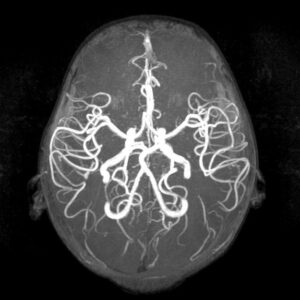

Aneurisma Cerebral

Un aneurisma es la dilatación de un vaso sanguíneo en el cerebro, generalmente una arteria cerebral. Estos aneurismas están formados por una debilidad de la pared de la arteria formando una dilatación que, debido a la debilidad de su pared, tiene riesgo de romperse.